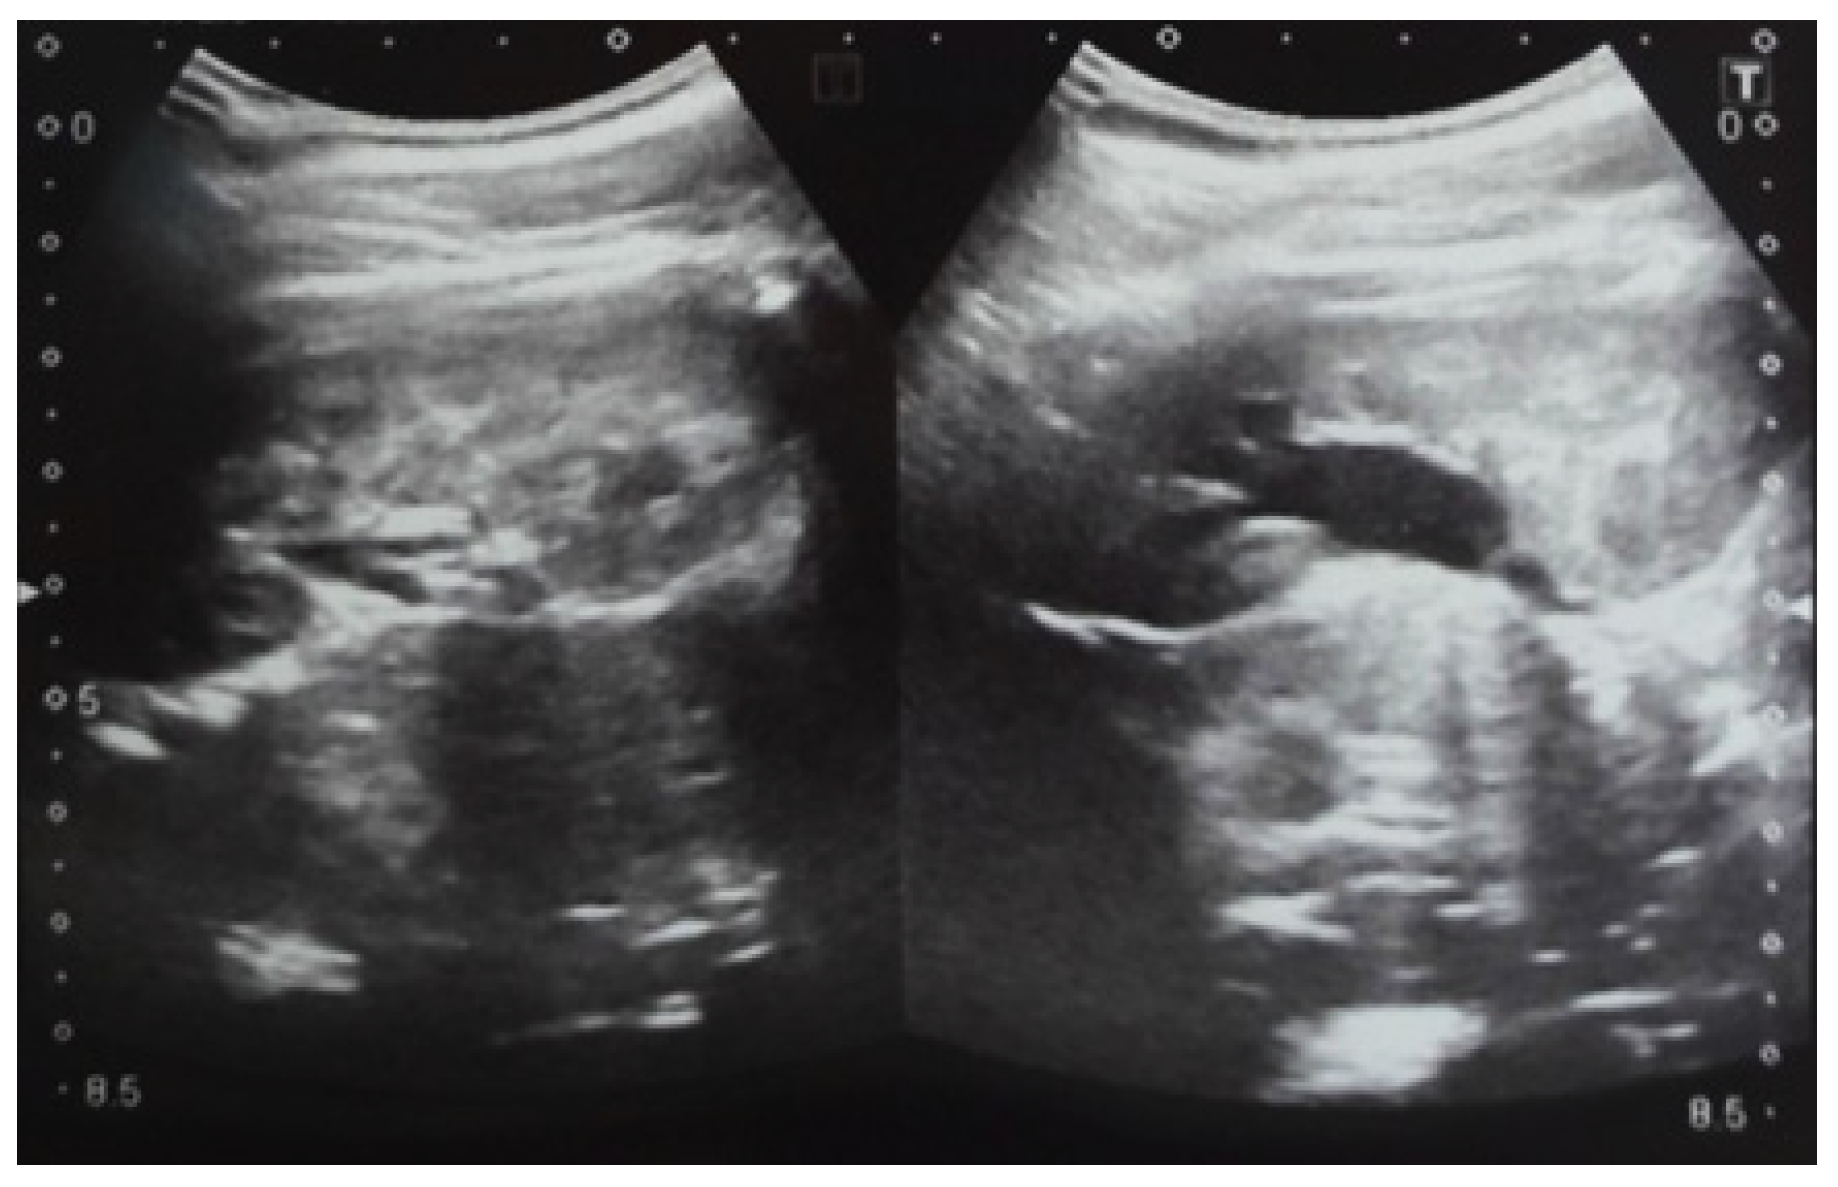

Our experience with congenital malformations of the urinary system refers to the following clinical case (Figure 2, Figure 3, Figure 4, Figure 5, Figure 6, Figure 7, Figure 8 and Figure 9). In the first case, during pregnancy, the 21-week ultrasound determined bilateral renal pyelectasia. The fetus had hydronephrosis on the right; at 31 weeks, it had bilateral hydrocalconephrosis; and at 32 weeks, bilateral pyelectasia. It suffered premature birth at 36 weeks, with complicated anomalies of the forces of contraction, prolonged birth, and birth weight of 2200 g. Postnatal ultrasonography was supplemented by intravenous urography, and bilateral hydronephrosis was determined. Hydrocalconephrosis on the left was discovered. The complete diagnosis was established: congenital renal malformation; bilateral pyelectasia; bilateral hydronephrosis; hydrocalconephrosis on the left; and severe reduced glomerular filtration rate (GFR), GFR > 2SD below mean.

Figure 9. Ultrasound of the urinary system in a 12-day-old newborn. Hydrocalconephrosis on the left (a) and ureteral hydronephrosis on the right (b).